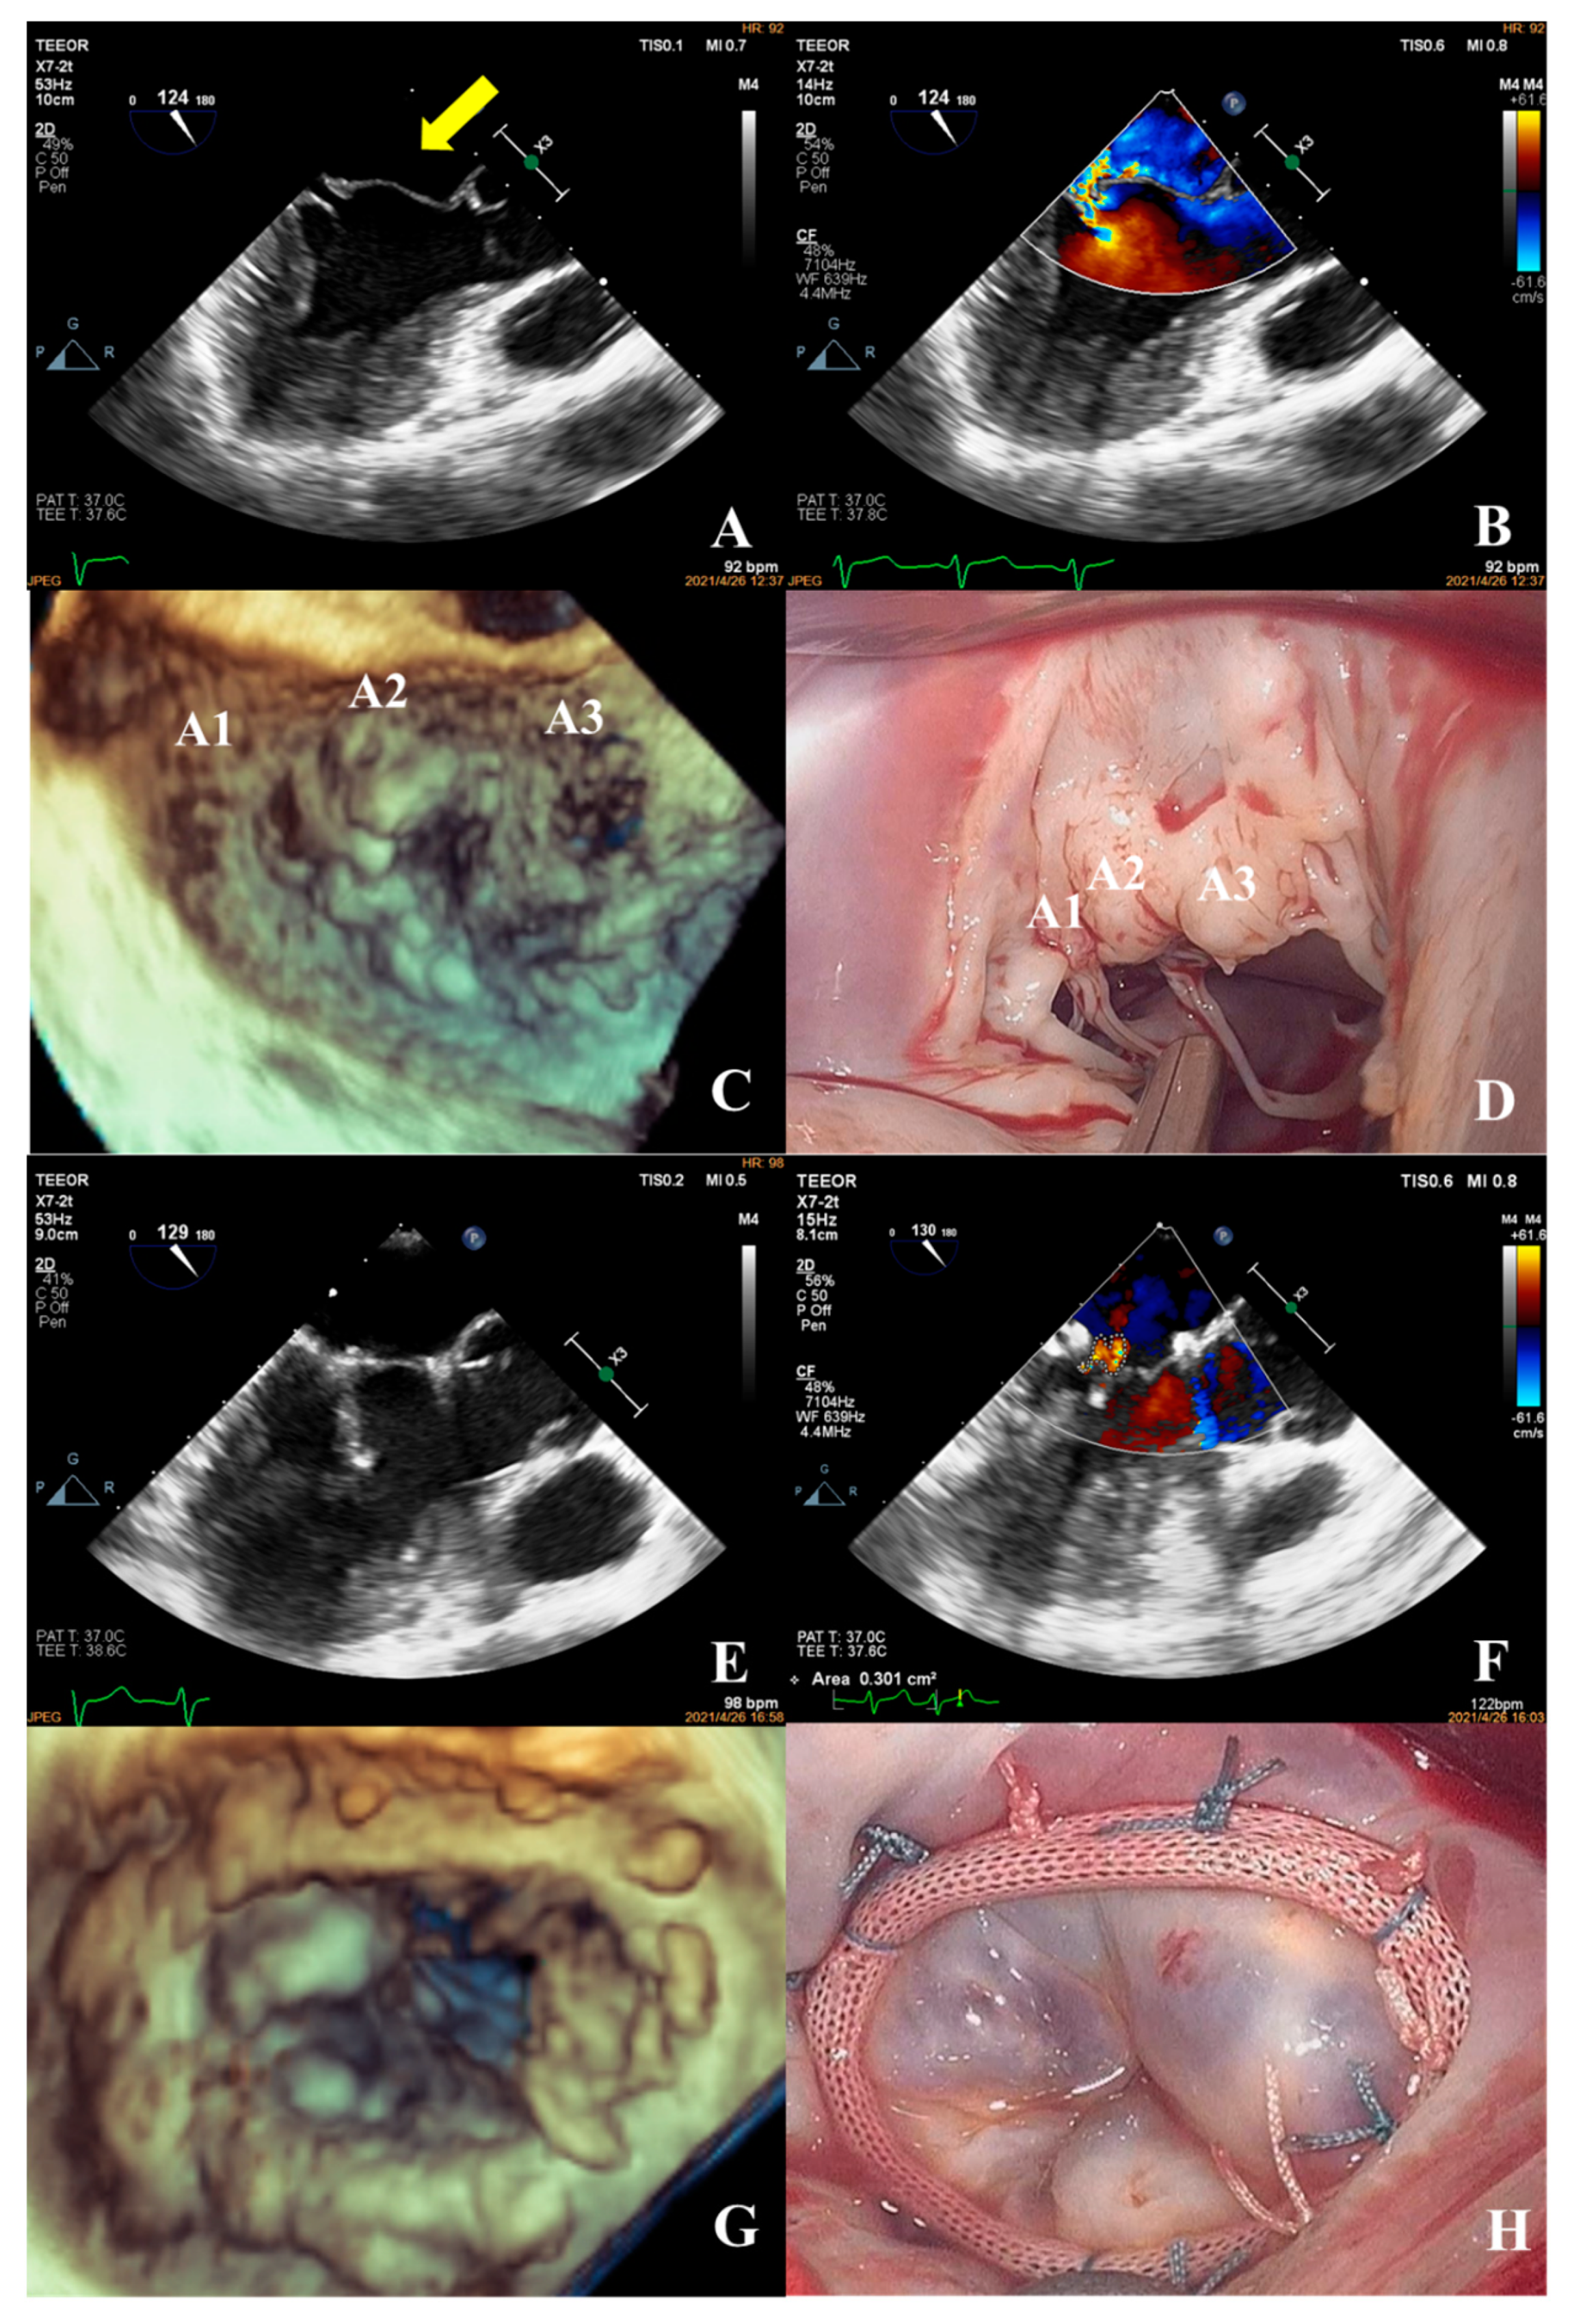

- The most common pathogenesis in the intermediate group was mitral valve prolapse involving multiple segments, with or without ruptured chordae tendineae. Mitral valve prolapses most often involved the posterior leaflet, specifically the P2 segment [17,19,22]. A patient with mitral valve prolapses involving the A1, A2, and A3 segments but no rupture of chordae tendineae had a complexity score of 7 (3 × 2 + 1) and a surgical technique score of 5 (2 × 1 + 1). The prolapsed leaflets were processed to reconstruct the artificial chordae tendineae and suture the sector junction to provide enough support when the leaflets were closed, thus increasing the coaptation area to reduce regurgitation (Figure 8).